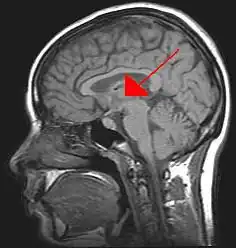

De thalamus,[7] afgeleid van het Griekse θάλαμος, thálamos, slaapkamer,[8] is een belangrijke hersenkern. Samen met de hypothalamus en de daaraan hangende hypofyse wordt het tot het diëncephalon, tot de tussenhersenen gerekend. De thalamus is een evolutionair gezien zeer oude hersenkern. Claudius Galenus (129-199) heeft over de thalamus geschreven.[9][10]

Er zijn eigenlijk twee thalami, in elke grote hersenhelft een. Ze horen bij de grijze stof van de hersenen. Ze nemen een groot deel van de tussenhersenen in beslag. Bij 70% van de mensen zijn ze met elkaar verbonden. Deze verbinding wordt in het Latijn de adhaesio interthalamica of ook wel massa intermedia genoemd. Ze zijn ongeveer vier centimeter lang, hebben de vorm van een ellipsoïde en zijn uit veel verschillende kernen van zenuwcellen opgebouwd. De derde ventrikel ligt tussen de twee thalami in.